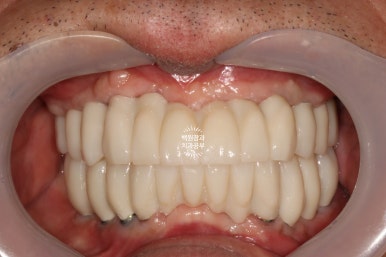

그리하여 완성된 최종보철물입니다!!

옛날부터 임플란트 틀니용으로 사용하시던 임플란트 3개는 임플란트 주위염이 조금 있어 약~간 쇠기둥 색깔이 보인다는 단점이 있긴 하지만, 다른 임플란트들은 꽤나 예쁘게 제작이 되었네요.

위 아래 교합면 사진을 보시면, 과연 이게 임플란트인가? 싶으실거에요. 치아에 지르코니아 크라운을 붙인 것과 큰 차이를 못느낄 정도로 정말 자기 치아같이 예쁘게 제작된 임플란트 크라운을 보실 수 있습니다!!